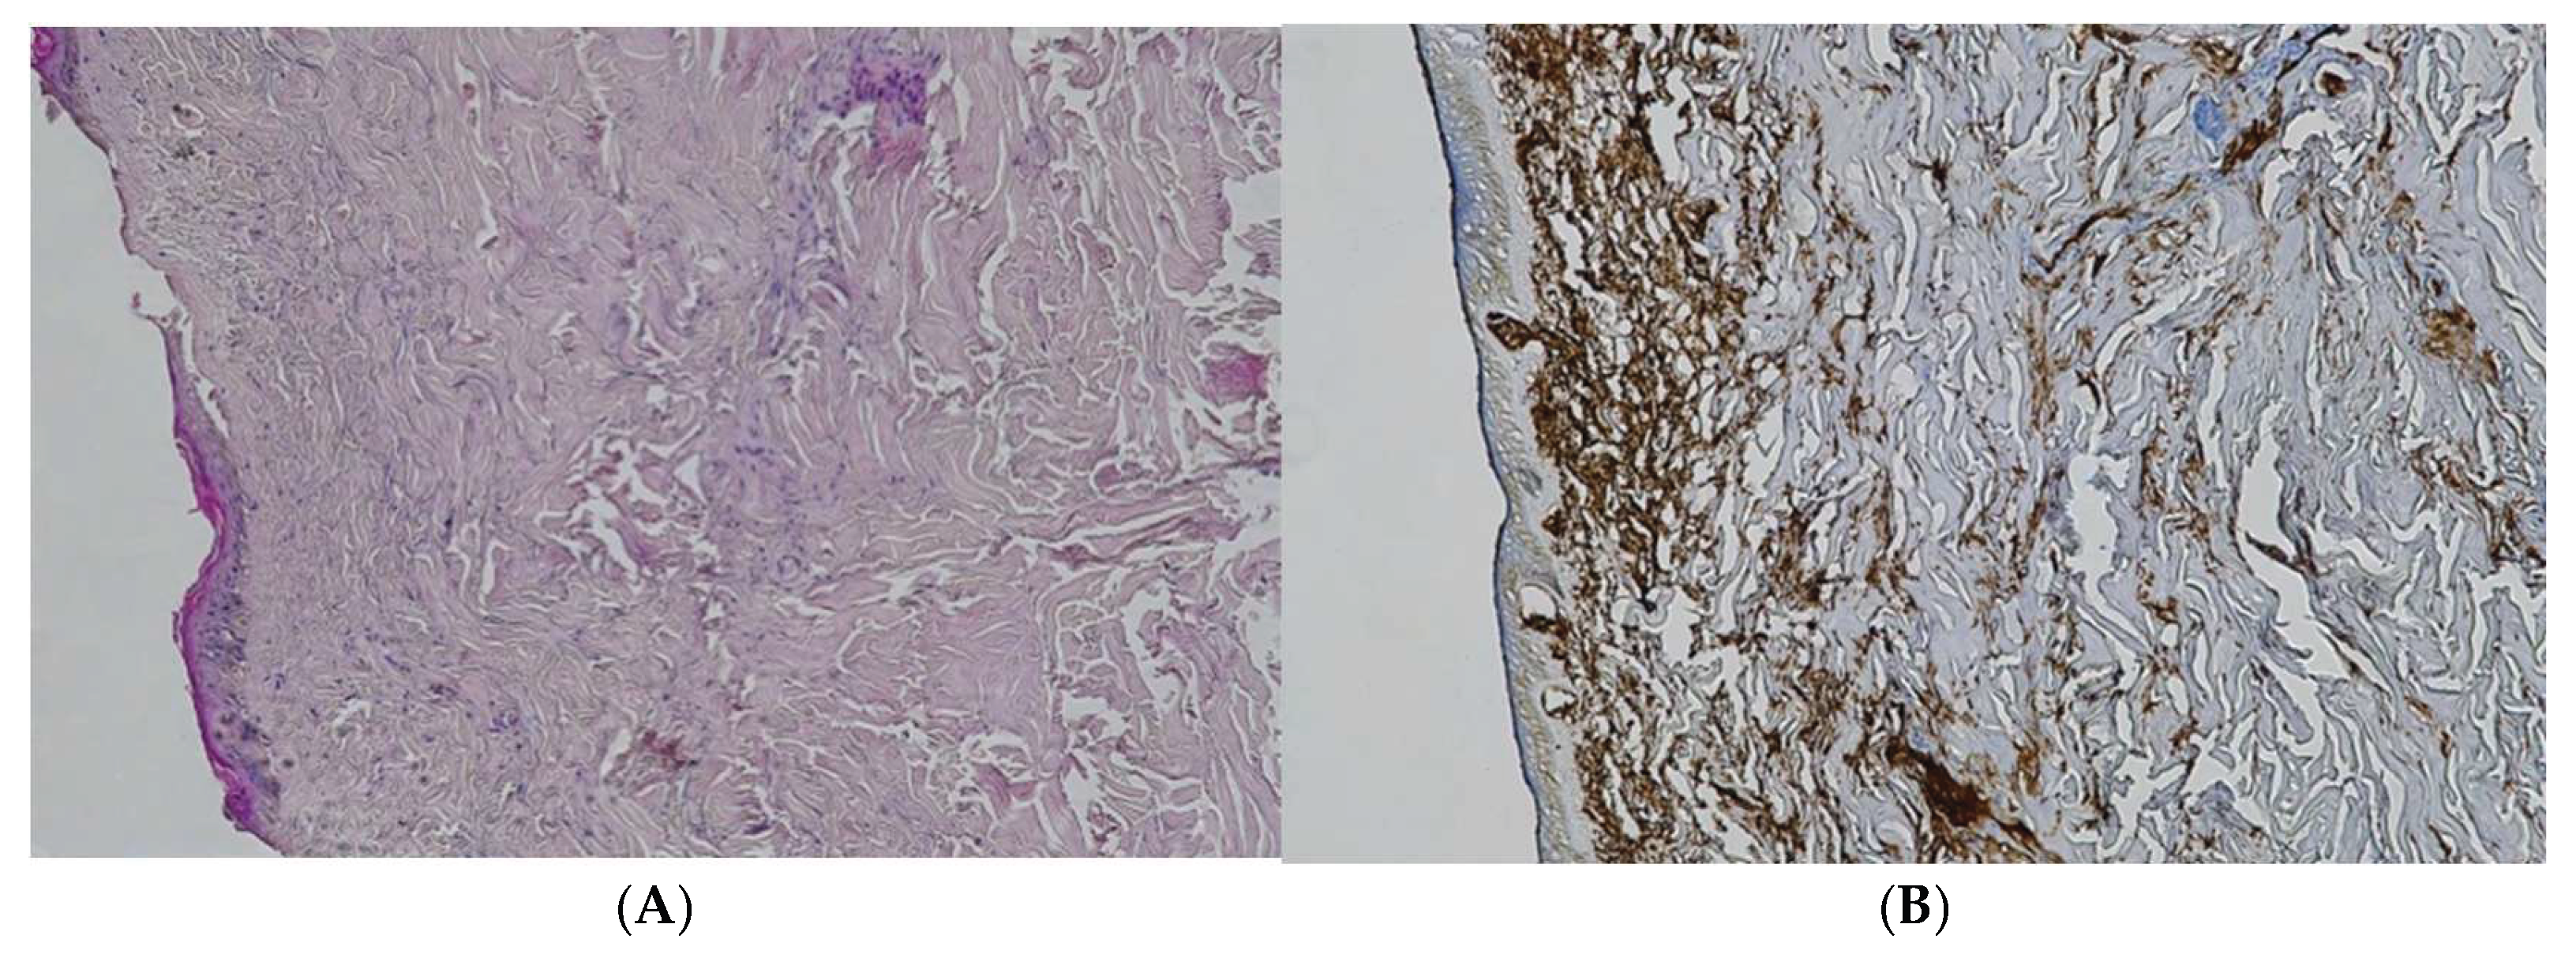

Figure 3. (A) Histological H&E staining of cutaneous tissue of a macroscopic area of discoloration sampled during the second phase of the autopsy, dubious of RBCs extravasation. (B) Immunohistochemical staining of cutaneous tissue with anti-GPA monoclonal antibody, positive for RBCs extravasation. The sample shows the presence RBCs in some of the areas that were marked as dubious in the H&E staining.

The suspected ecchymotic areas collected during the preliminary assessment were subjected to routine H&E staining and unequivocally confirmed the presence of extravased red blood cells.

Conversely, samples collected after the freeze-thaw cycle were negative for red blood cells with H&E staining. The immunohistochemical staining with anti-GPA antibody was then employed with positivity on most of the samples.